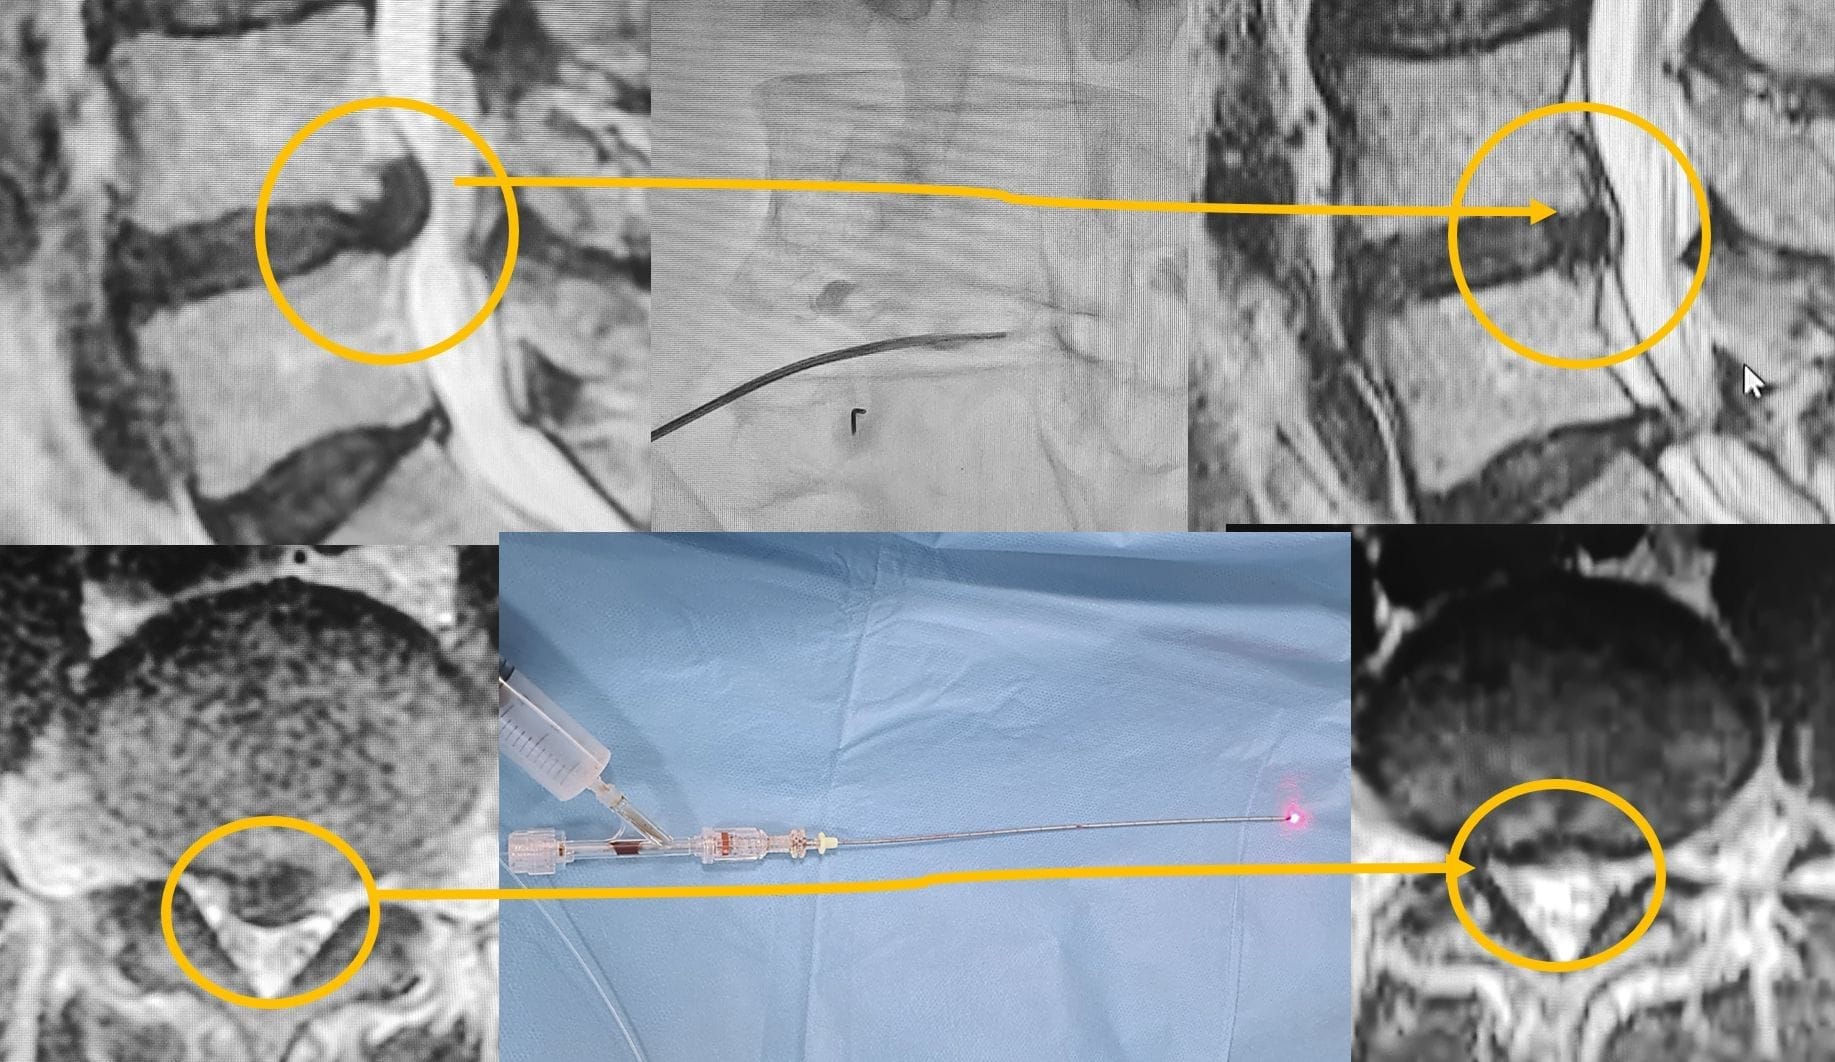

Laserbehandlung zur Bandscheibenverkleinerung:

Bei dieser Methode wird die Nadel ähnlich wie bei der Radiofrequenz in die Bandscheibe eingeführt, und durch die Nadel wird eine Laserfaser geführt, die Wärme überwacht und eine bestimmte Energiemenge in die Bandscheibe einbringt, um die Bandscheibe langfristig zu verkleinern.

- Laser-Diskektomie: Mit einer Lasernadel wird Wärmeenergie in die Bandscheibe eingebracht, um eine Schrumpfung der Bandscheibe zu erzielen.

Dieser Eingriff wird unter der Aufsicht eines Arztes im Operationssaal durchgeführt. Ein Fluoroskopiegerät ermöglicht es dem Arzt, das Zielgebiet während des Eingriffs präzise zu erkennen. Eine Allgemeinanästhesie ist nicht erforderlich. Falls nötig, werden dem Patienten sedierende Medikamente verabreicht, um ihn zu beruhigen. Der Eingriff wird mit speziell entwickelten Kanülen und Elektroden durchgeführt.

- Platzierung der Kanüle: Die Kanüle wird präzise in das Zielgebiet eingeführt.

- Verwendung von Elektroden: Über die Elektroden werden Radiofrequenzwellen an den Zielnerv gesendet. Diese Wellen reduzieren den Druck auf den Nerv und lindern den Schmerz.